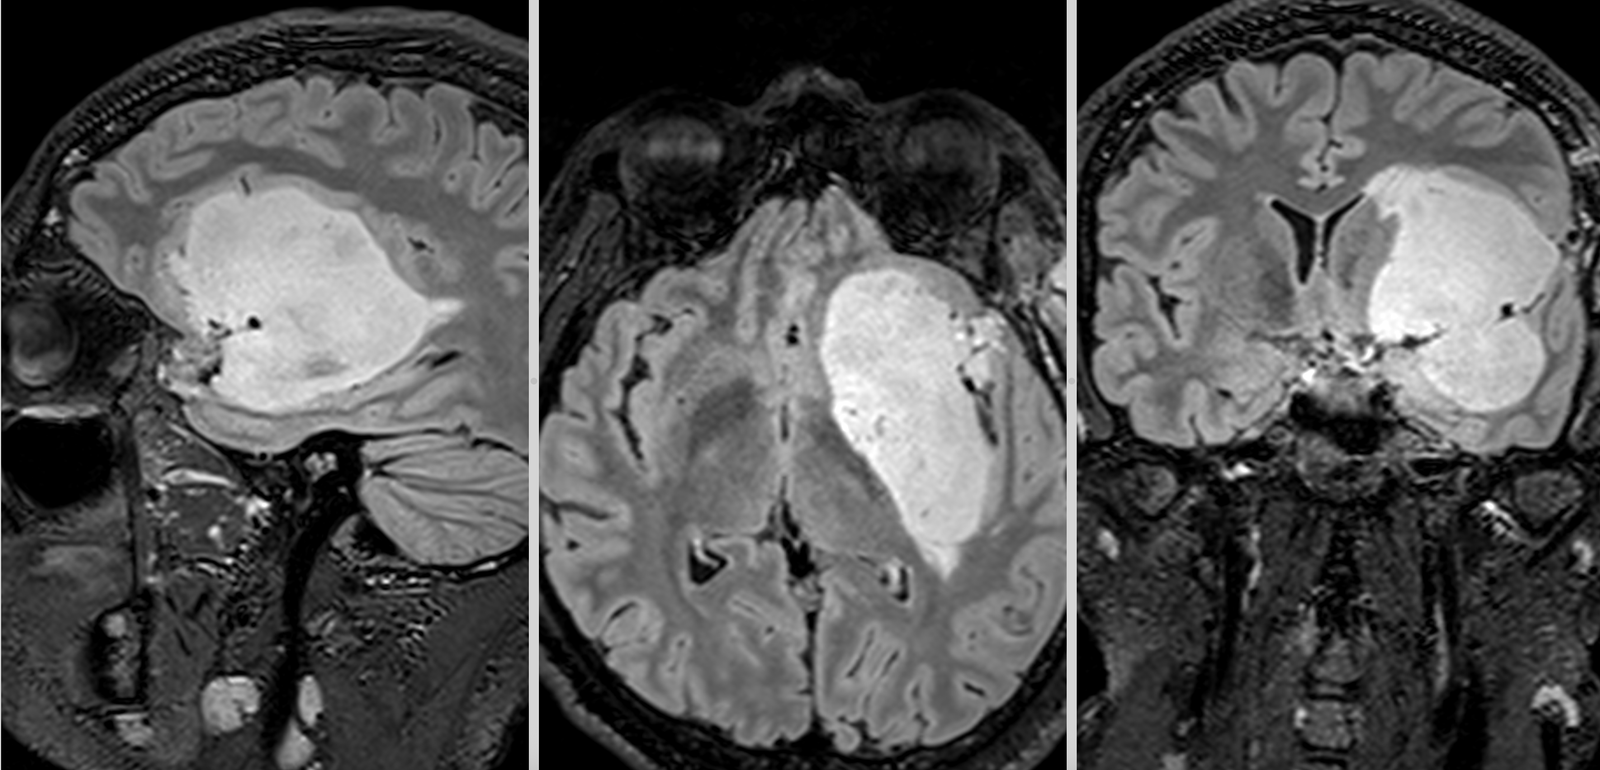

Oligodendrogliom temporal stâng

RMN cerebral cu contrast – metoda standard pentru caracterizarea glioamelor. Glioamele de grad mic apar ca leziuni hipointense pe T1, hiperintense pe T2, fără captare de contrast. În mod uzual se consideră că dacă un gliom de grad mic are o zonă cu priză de contrast pe RMN el este de grad III – anaplazic (grad înalt).